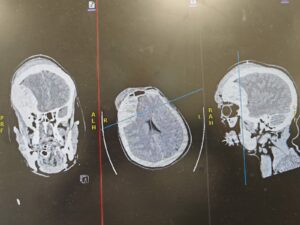

وبيّن التجمع على الفور تم وُضع المستفيد على جهاز التنفس الصناعي، وأُجريت له الفحوصات الطبية والأشعة اللازمة، والتي كشفت عن وجود نزيف حاد فوق الأم الجافية في الجهة الأمامية الصدغية اليمنى، تسبب في انزياح المخ، إلى جانب كسور متعددة في الجمجمة ممتدة من أعلى الرأس حتى مقدمته والجيوب الأنفية، وكسور في العظام المحيطة بحجاج العين، بالإضافة إلى كسر في الفقرتين العنقيتين السادسة والسابعة.

وأضاف تجمع المدينة أنه فور تشخيص الحالة جرى تجهيز غرفة العمليات بشكل عاجل، ونُقل المستفيد لإجراء عملية جراحية طارئة لإنقاذ حياته، تم خلالها فتح الجمجمة وتفريغ النزيف من الجهة الأمامية الصدغية اليمنى وصولًا إلى قاع الجمجمة خلف العين اليمنى. واستغرقت العملية ساعتين، تكللت – بفضل الله – بالنجاح مع السيطرة الكاملة على النزيف.